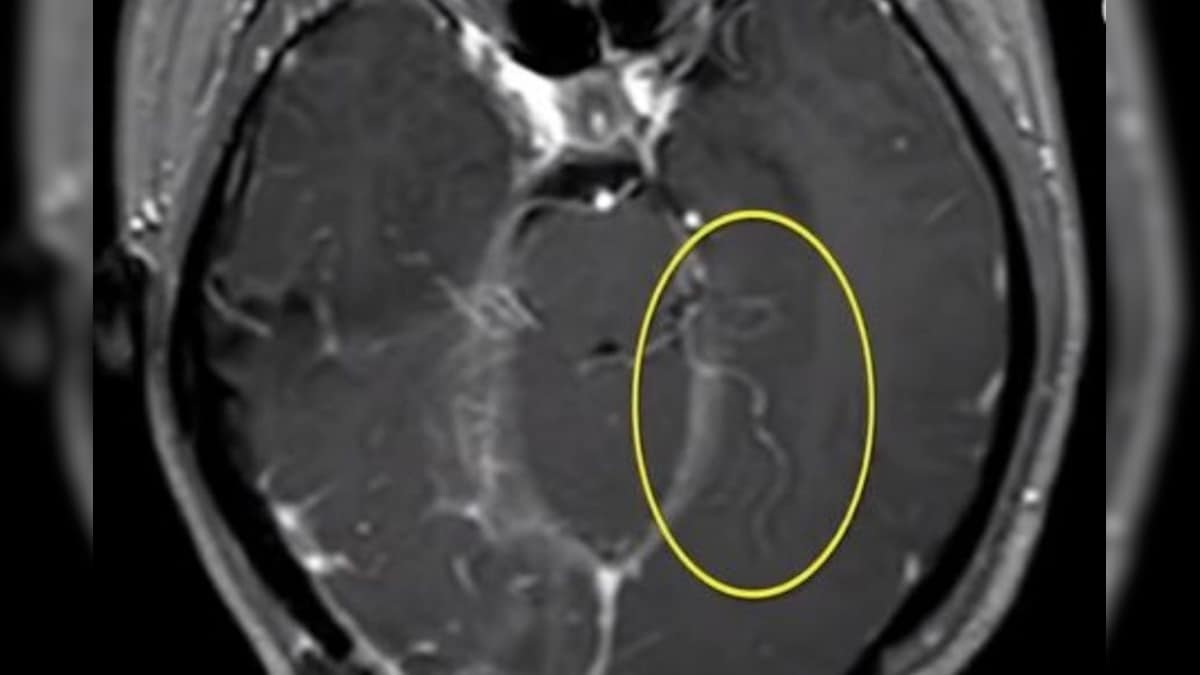

Worm on brain Doctors were shocked and nauseous when they found an 8cm parasite wiggling on Can Worms Affect Your Brain There are “legions” of organisms that can affect the brain, said scott gardner, a. There are much more common parasites which can infect your body and brain and ways you can minimise your risks of being infected with one. Experts say that even if you do have a parasite in your head, you shouldn’t necessarily freak out. This article reviews. Can Worms Affect Your Brain.

Neurological Symptoms Lead to Discovery of Unusual BrainInvading Worm Can Worms Affect Your Brain There are much more common parasites which can infect your body and brain and ways you can minimise your risks of being infected with one. From worms that devour brain cells to viruses that bring on crippling paranoia, these creatures are every bit as ghoulish as those in any fireside ghost story. Brain parasites encompass far more than worms. Headlines. Can Worms Affect Your Brain.

Parasitic Roundworm from Python Found in Human Brain Neuroscience News Can Worms Affect Your Brain From worms that devour brain cells to viruses that bring on crippling paranoia, these creatures are every bit as ghoulish as those in any fireside ghost story. Philip budge, md, phd, assoc. This article reviews how parasites affect the human nervous system, with a focus on four parasitic infections of major public health. Headlines about brain worms can be alarming.. Can Worms Affect Your Brain.

Tapeworm infection Rare brain worm took 4 years to crawl across UK man’s brain YouTube Can Worms Affect Your Brain Headlines about brain worms can be alarming. Experts say that even if you do have a parasite in your head, you shouldn’t necessarily freak out. From worms that devour brain cells to viruses that bring on crippling paranoia, these creatures are every bit as ghoulish as those in any fireside ghost story. There are “legions” of organisms that can affect. Can Worms Affect Your Brain.